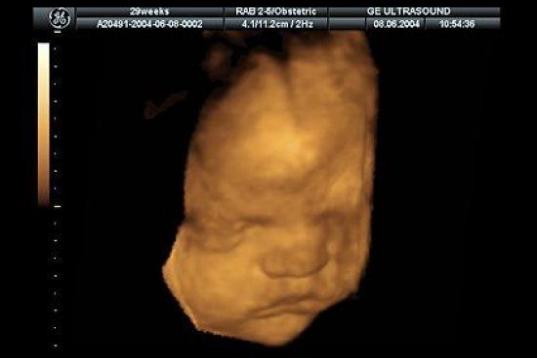

En esta galería puedes ver en fotos como es el desarrollo de un feto de semana en semana:

Desarrollo del feto, en fotos